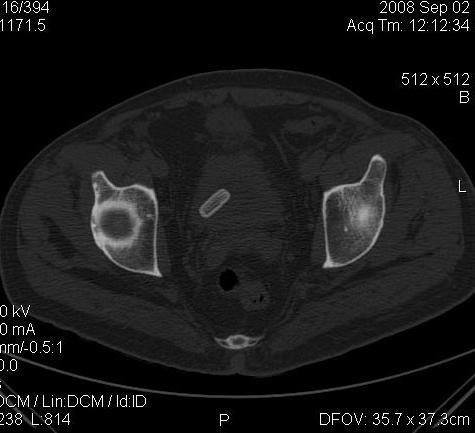

КТ Малого таза.

Что в мочевом пузыре? :?: ;)

Я тоже так думал! Урологи выполнили цистоскопию, оказалось камень, такой причудливой формы.